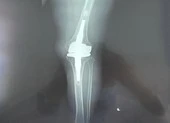

Bệnh nhân H. được chẩn đoán bị gãy xương đùi phải, gãy hai xương cẳng chân phải được xuyên kim kéo tạ, dự kiến được phẫu thuật kết hợp xương sau. Hiện tình trạng bệnh nhân tạm ổn và đang điều trị tại Khoa Chấn thương Chỉnh hình của BV Nhân dân Gia Định.

Cô gái đang được điều trị ở Bệnh viện Nhân dân Gia Định. Ảnh: BVCC